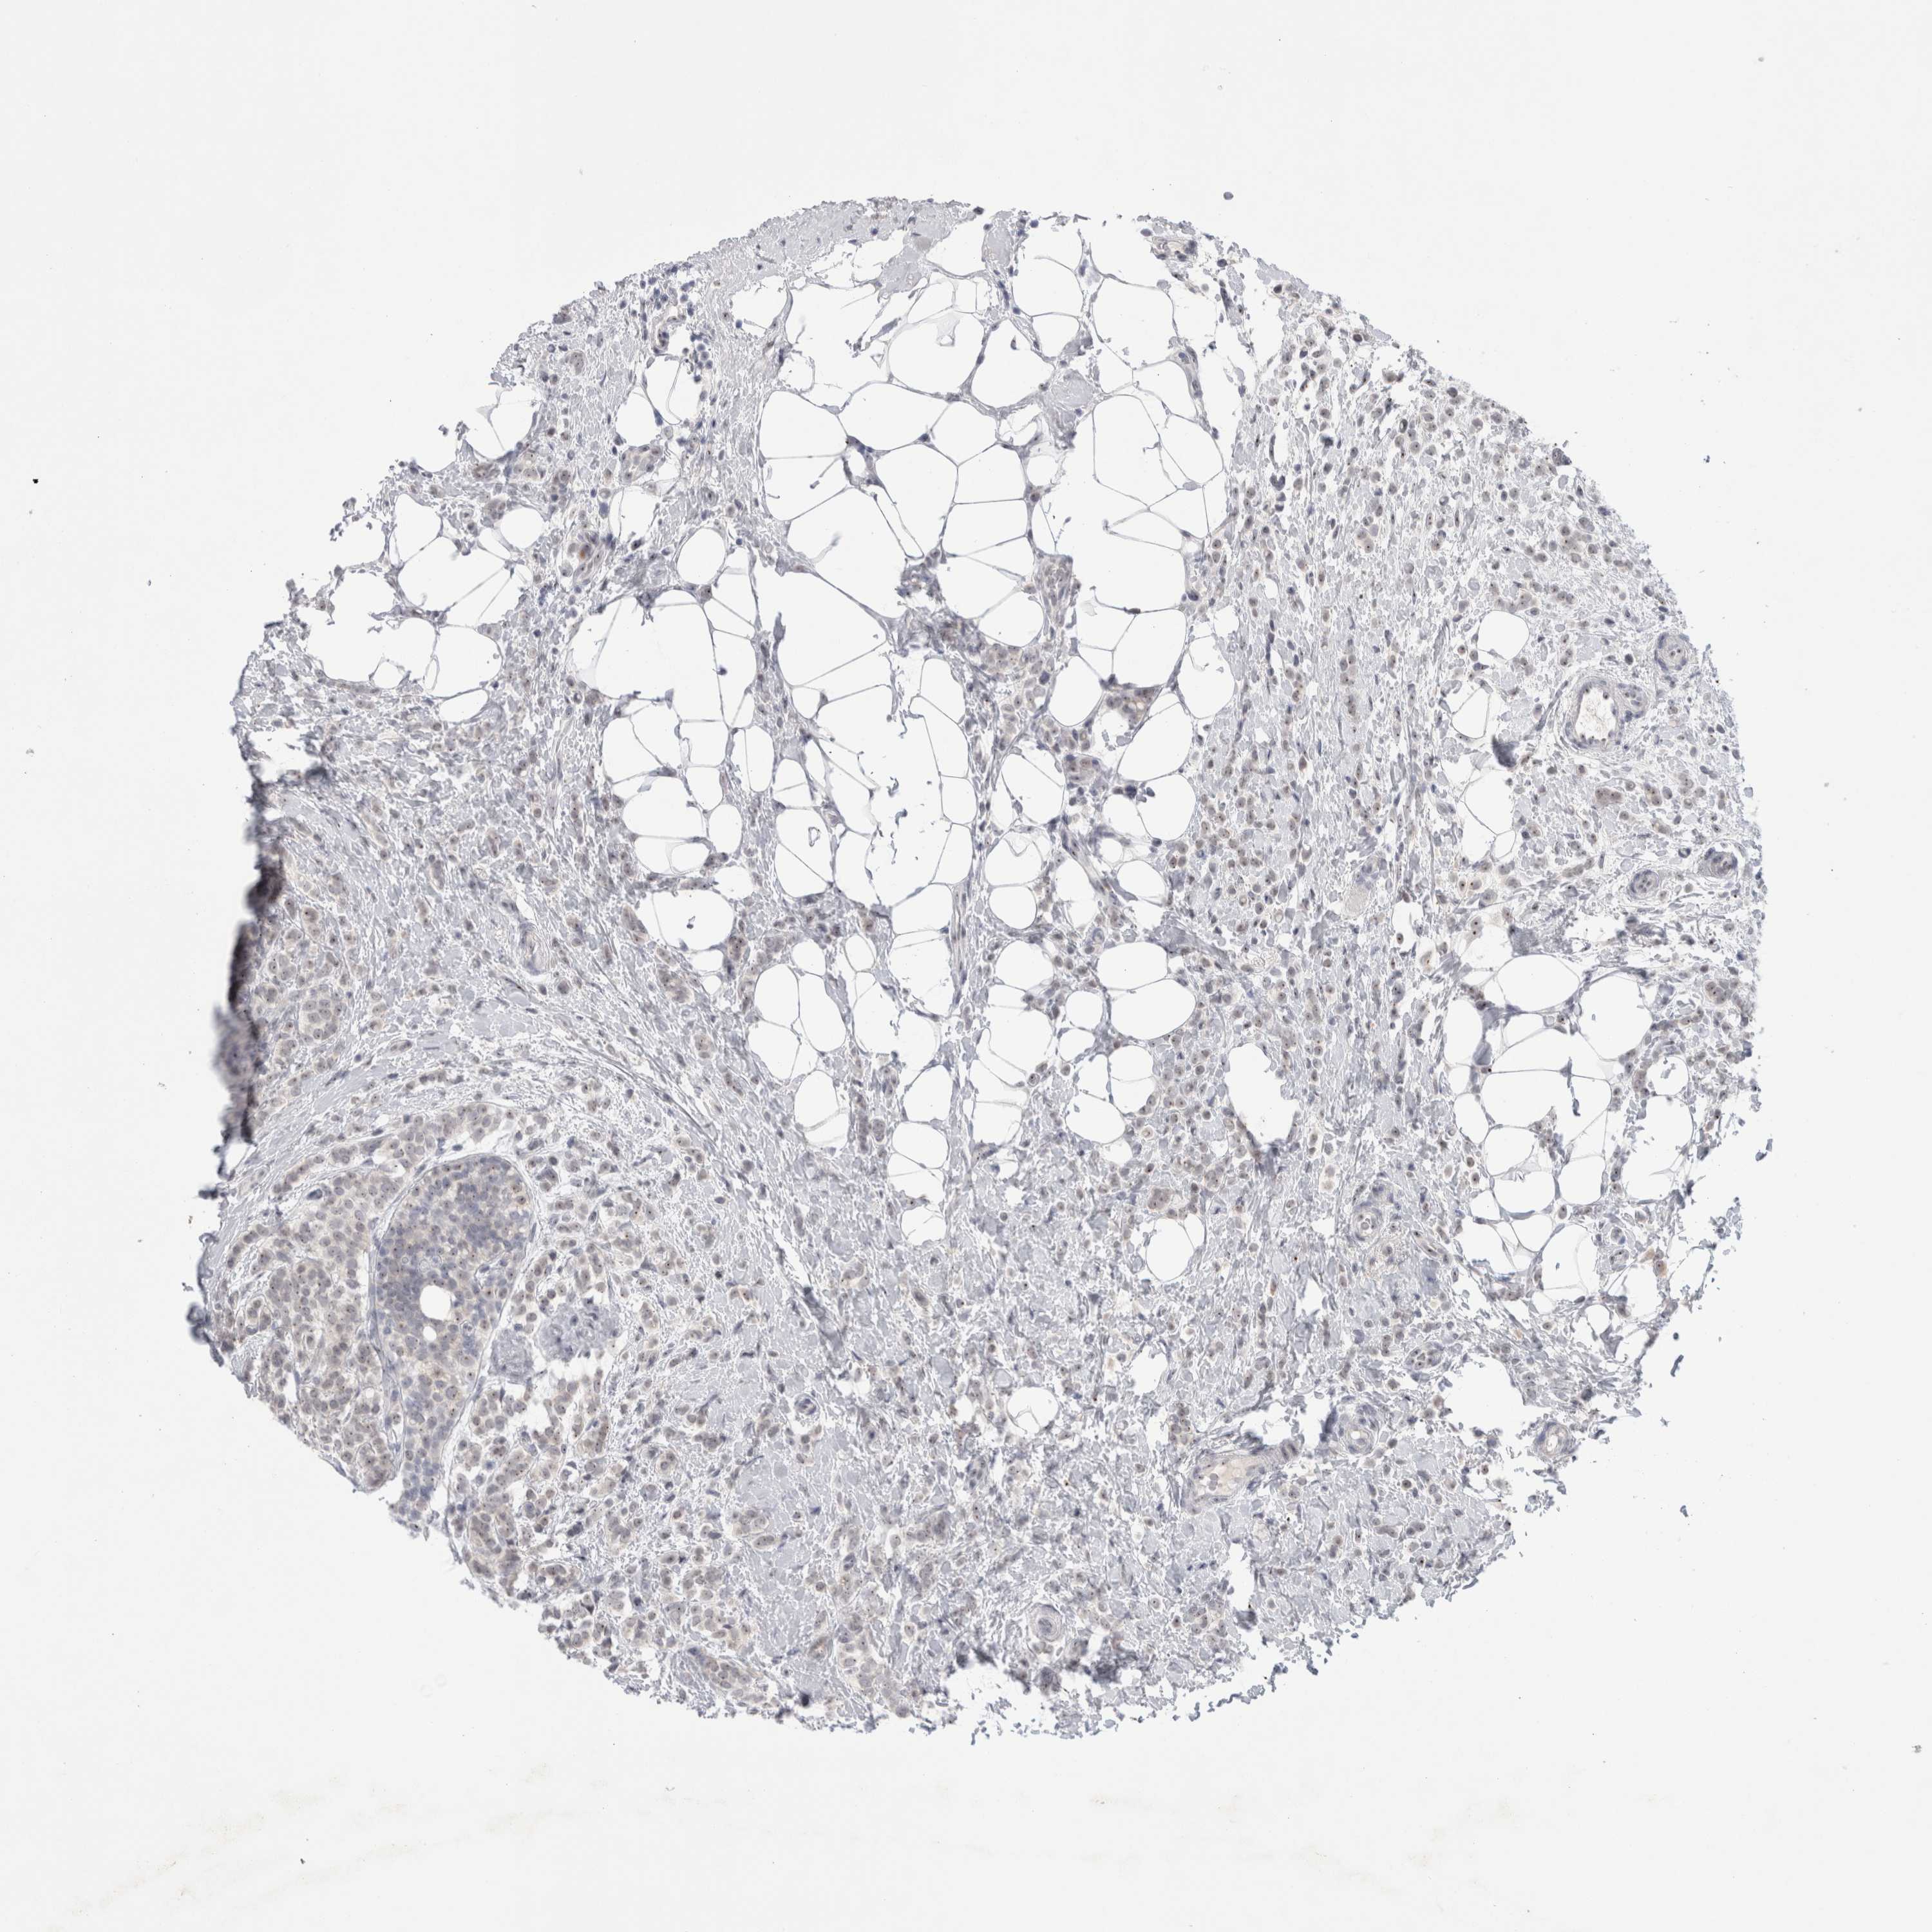

CANCER BREAST CANCER Show tissue menu

BRCA TCGA BRCA VALIDATION PROTEIN EXPRESSION